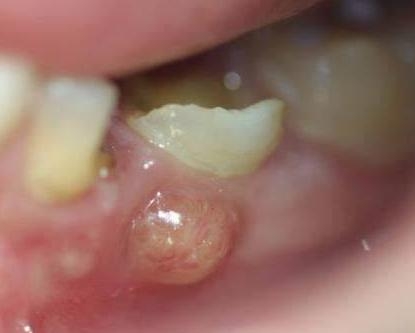

根尖周病

根尖周病是牙齿根尖周围组织的一种炎症性疾病,可以是细菌感染,也可以是创伤、牙隐裂等问题导致,严重的根尖周病可大量吸收破坏牙齿根尖周围的骨组织,导致患牙无法固定在牙槽骨里而松动。

未及时治疗的龋病、牙髓病,细菌可沿根管内感染到根尖,因此为了有效防止根尖周病,对于龋齿、牙髓炎等疾病需要尽早治疗,避免炎症发展至根尖。

根尖周炎导致的牙龈“鼓包”